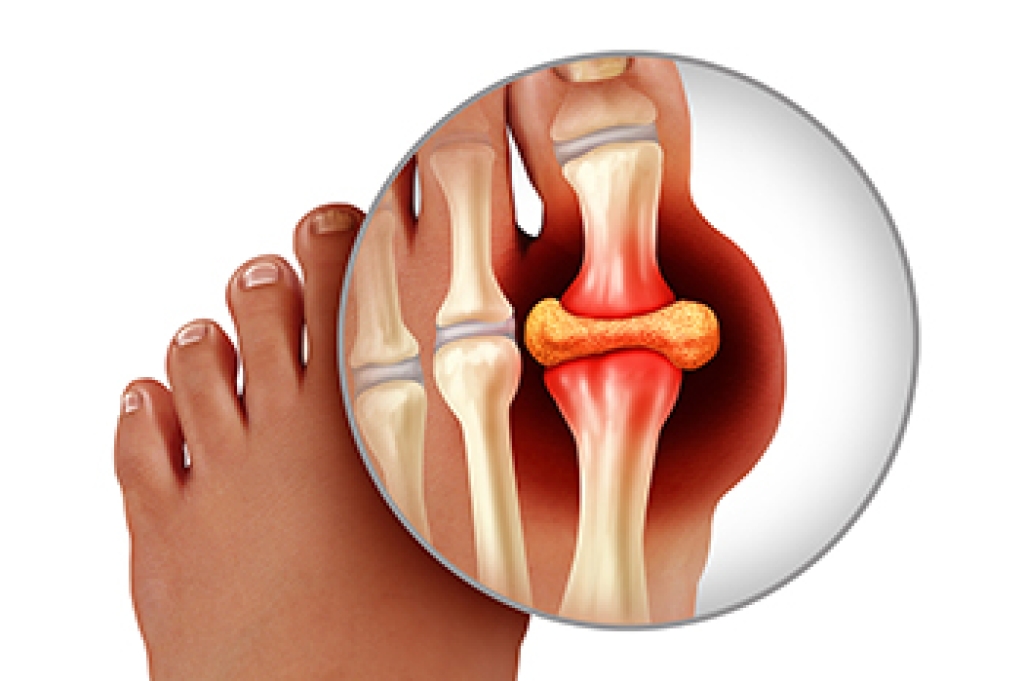

Gout is a type of arthritis caused by a buildup of uric acid crystals in the joints, often affecting the big toe, but also the foot and ankle. Symptoms include sudden, severe pain, redness, swelling, and warmth in the affected joint, making walking or standing difficult. Risk factors include a diet high in purines, obesity, genetics, alcohol consumption, and certain medical conditions. Repeated gout attacks can lead to joint damage, decreased mobility, and long-term discomfort. A podiatrist can diagnose gout, recommend lifestyle adjustments, prescribe medication, and provide care to reduce pain and prevent future attacks. Early intervention helps protect joint health and improve mobility. If you have gout symptoms in your big toe or foot, it is suggested that you promptly consult a podiatrist who can help you to manage this painful condition.

Gout is a type of arthritis caused by a buildup of uric acid in the bloodstream. It often develops in the foot, especially the big toe area, although it can manifest in other parts of the body as well. Gout can make walking and standing very painful and is especially common in diabetics and the obese.

Gout can easily be identified by redness and inflammation of the big toe and the surrounding areas of the foot. Other symptoms include extreme fatigue, joint pain, and running high fevers. Sometimes corticosteroid drugs can be prescribed to treat gout, but the best way to combat this disease is to get more exercise and eat a better diet.